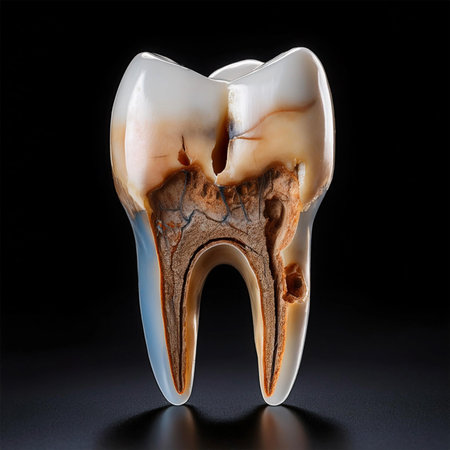

Tooth decay on black background. Macro shot of a decayed teeth till root after extraction of dentist. Real tooth anatomy due lack of care. Top view of caries teeth texture on black paper. Dental care.

The image depicts a tooth with severe tooth decay, characterized by visible cavities and brown discoloration.

This detailed image shows a cross-section of a tooth's anatomy, highlighting areas affected by tooth decay and cavities. It is visually informative and crucial for understanding dental issues.

This detailed image shows a cross-section of a tooth's anatomy, highlighting areas affected by tooth decay and cavities. It is visually informative and crucial for understanding dental issues.

The image depicts a tooth with severe tooth decay, characterized by visible cavities and brown discoloration.

This image provides a detailed cross-section view of a human tooth, revealing the inner anatomy including the root pulp and surrounding bone structures. It is an educational and informative visual aid